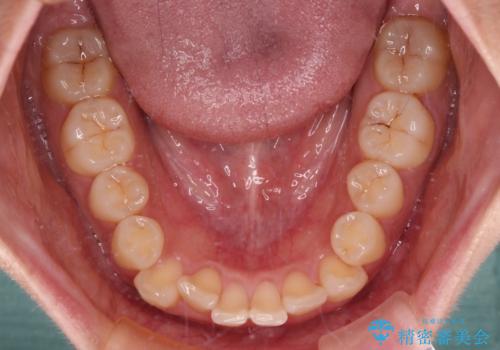

上下前歯のデコボコ ワイヤー装置で楽して改善

- 上下前歯のデコボコを気にして来院された患者様です。

治療中は大きなトラブルもなく、予定の1年半でスムーズに治療を終えることができました。